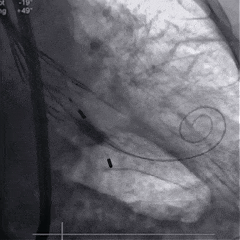

术中影像

根部造影

球囊预扩

瓣膜稳定释放

瓣膜展开后造影

再次造影,确认瓣膜位置

稳定脱钩

最终造影,瓣膜位置良好,无明显瓣周漏

外周血管检查